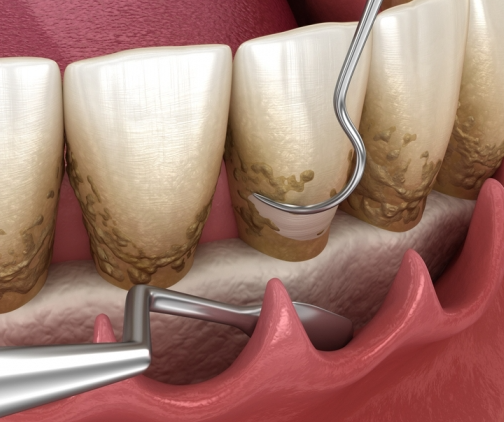

擦牙容易出血,係牙周炎早期最直觀表現,當牙齦出現紅腫,伴有口臭同化膿時,牙周炎好可能已經發展到中期,當牙齒嚴重鬆動,脆弱到斷裂時,牙周炎已達到晚期。

牙周病係目前常見嘅口腔疾病之一,也係成人缺牙嘅主要原因,牙周病引起嘅牙槽骨吸收同牙齦萎縮係不可逆轉嘅,牙周病也係一種無意識嘅疾病,許多人沒有發現牙周病,直到發現情況已經非常嚴重,因此,牙周病嘅早期發現同早期治療係非常重要嘅。